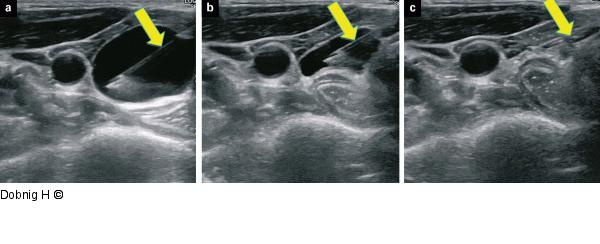

Abbildung 7a-c: Alkoholablation - Schilddrüse Entleerung der Zyste immer unter idealen Sichtbedingungen. Die Nadelspitze liegt im Zystengrund und ist immer sichtbar (Pfeile). (c) zeigt eine maximal entleerte Zyste. Die Nadel verbleibt vor Ort. |